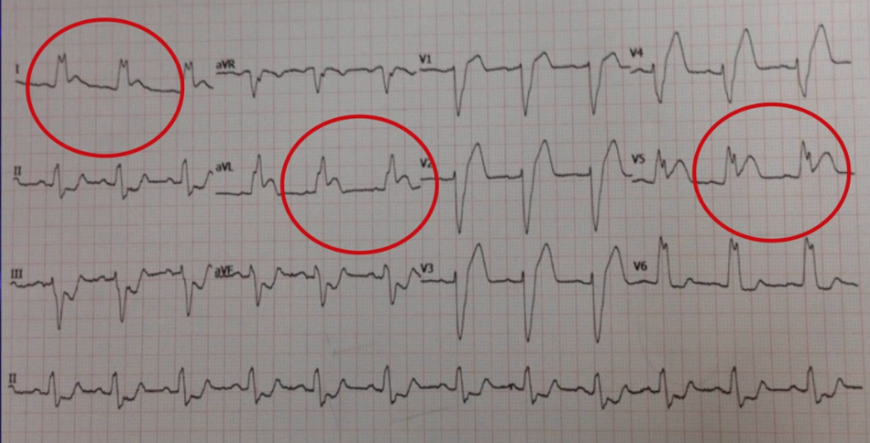

There is 1mm concordant ST elevation in aVL, V4-6 (= 5 points)

There is 1mm concordant ST elevation in aVL (= 5 points)

There is concordant ST depression in V1-3 (= Sgarbossa positive).

There is 1mm concordant ST elevation in aVL, V5-V6 (= 5 points)

There is 1mm concordant ST elevation in I, aVL, V5 (= 5 points)

There is concordant ST depression in V1-3 (= Sgarbossa positive).